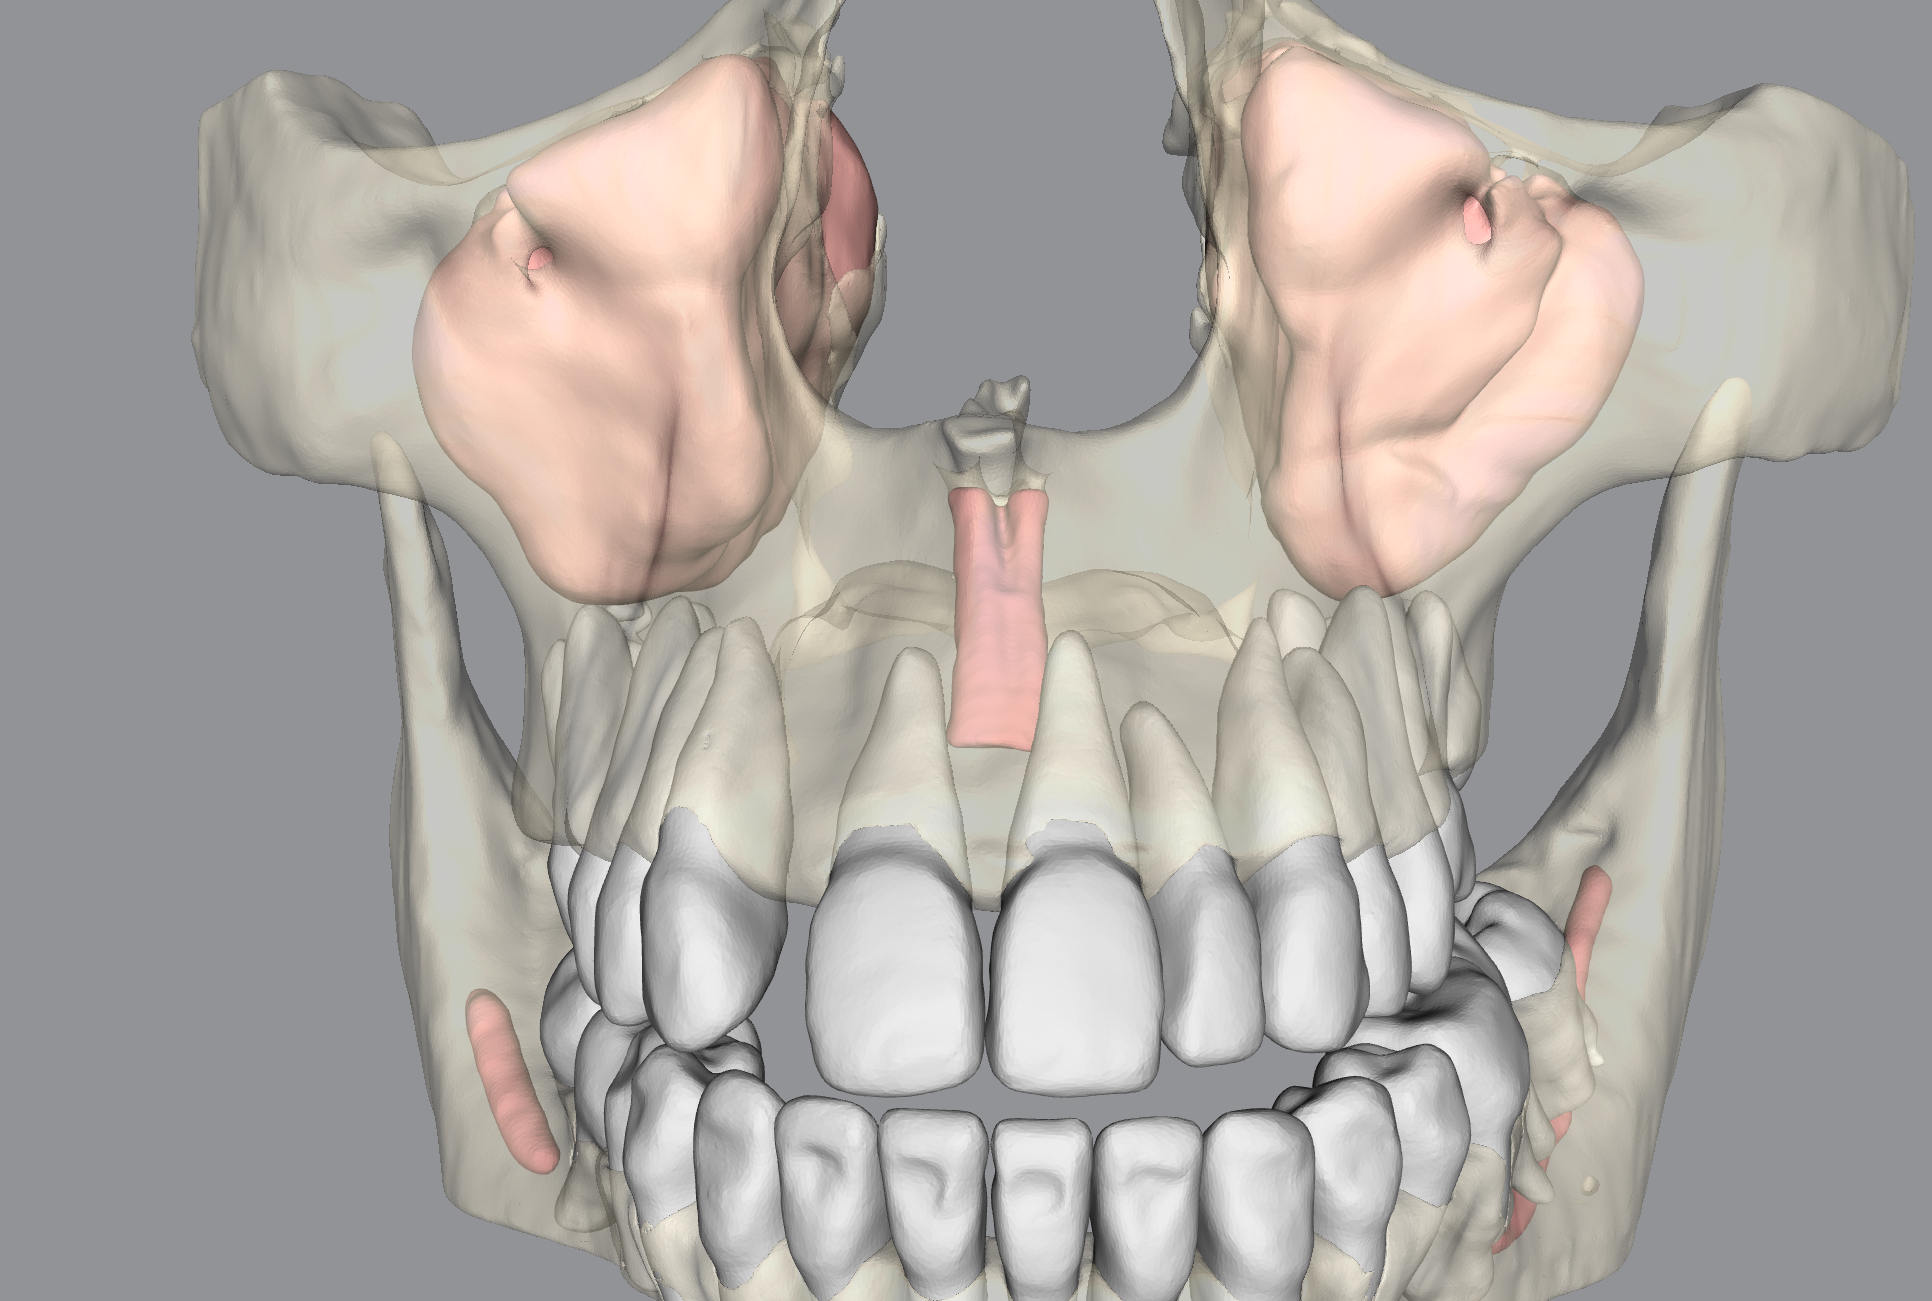

Diagnoplan is specialized in providing digital dentistry online services, including reporting, designing, and planning. Starting from diagnostic reporting , planning, and AI services till designing a final appliance. We use the latest technology and advanced software to design precise appliances tailored to your patient, including surgical guides, PSIs, orthognathic wafers and many more.